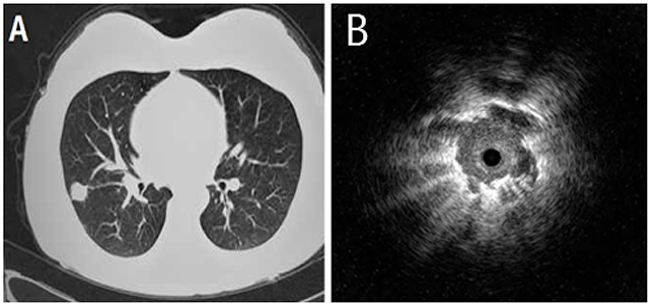

We analyzed the influencing factors including size of the lesions, ultrasonography appearances and localization. Diagnostic yield of the SPNs in diameter of 20-30mm was 89.6 % (86/96), while the diameter of 20 mm or less was 57.1 % (48/84), the difference was statistically significant (χ2 = 12.39, P < 0.01). Lesion in which the probe was advanced to within the lesion, as determined from the EBUS image, had a higher diagnostic yield (102 of 110 lesions, 92.7 %) than when the probe was adjacent to the lesion on the EBUS image (32 of 46 lesions, 69.6 %) [χ2 = 7.18, P < 0.01] (Figure 1A). Diagnostic yield of the central lesions (medial 1/2 of lung field) on high resolution CT images was 83.3 % (100/120), while peripheral lesions (lateral 1/2 of lung field) was 56.6 % (34/60), the difference was statistically significant (χ2 = 7.48, P < 0.01) (Figure 1B and Table 2).

Figure 1: A 52-year-old male who underwent right middle lung lobectomy for pulmonary adenocarcinoma. (A) Chest computed tomography showed a pulmonary nodule of 26 mm in diameter. (B) Endobronchial ultrasonography showed a low echoic nodule surrounded by a strong reflected interface produced between the aerated lung and the lesion.